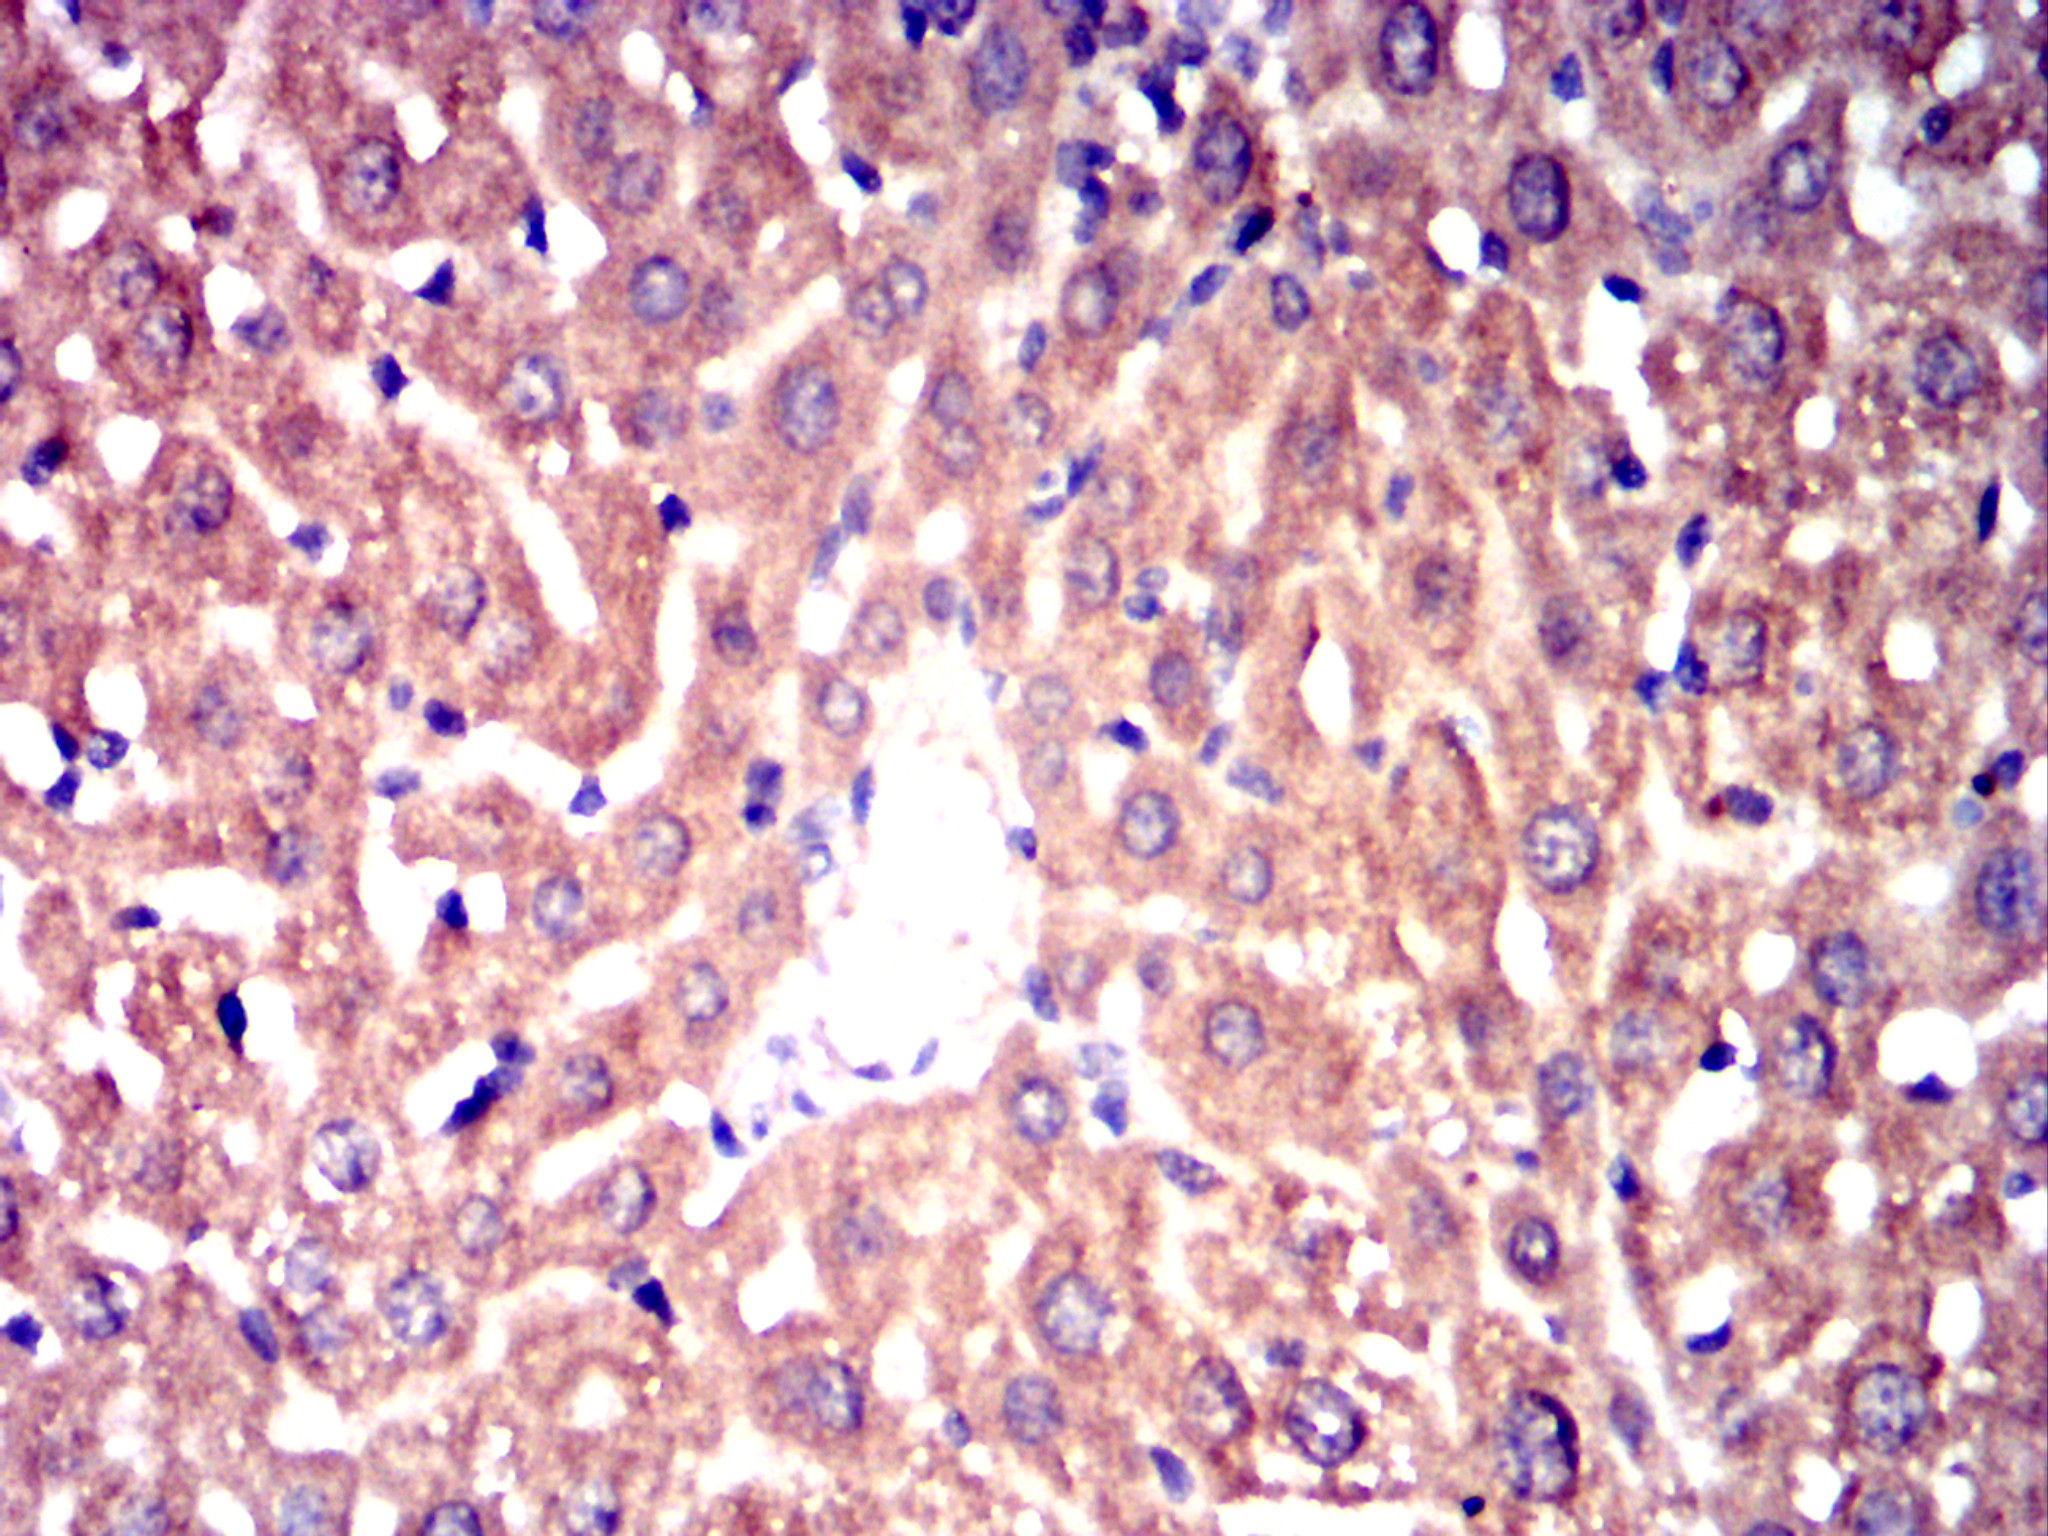

-

Immunohistochemical analysis of paraffin-embedded mouse liver tissues using CHRM3 mouse mAb with DAB staining.